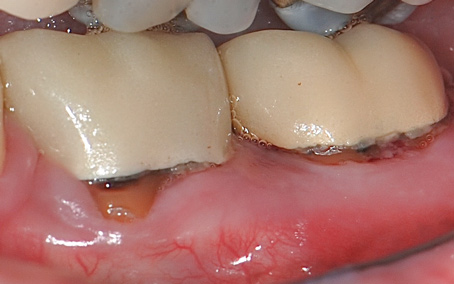

Regarding furcation defects, based on the available evidence, the AAP workshop concluded that regenerative therapy is a viable option to achieve predictable outcomes for their treatment in certain clinical scenarios.13 Periodontal regeneration has been established as a viable therapeutic option for the treatment of various furcation defects, including Class II defects, which represent a highly predictable scenario. The application of combined therapeutic approaches (ie, barrier, bone replacement graft with or without biologics) appears to offer an advantage over monotherapeutic algorithms.13 Figure 12 through Figure 15 depict the periodontal regenerative treatment of two previously restored teeth with intrabony and furcation defects using mineralized FDBA and EMD.

(12.) Pretreatment photograph of two previously restored teeth exhibiting gingival recession and probing depths equal to or greater than 15 mm.

Figure 12

(13.) Pretreatment radiograph showing intrabony and furcation defects.

Figure 13